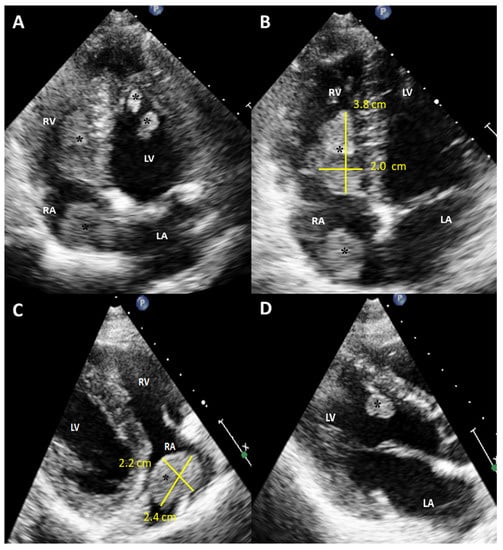

Figure 1. Initial scan: Transthoracic echocardiogram images, four chamber apical view (A,B) and parasternal long axis view (C,D). Multiple masses in the cardiac chambers are marked with black asterisks. A 30-year-old Caucasian man with a history of an in-situ melanoma of the forehead, which was surgically excised four years earlier, was referred for cardiac evaluation because of tachycardia and elevated levels of serum troponin. The patient had presented three months ago to the oncology clinic, with dry cough and pigmented skin nodules on the left shoulder, left forearm, chest, and forehead. Abdominal and brain computed tomography (CT) scans showed several metastatic lesions in the liver, the spleen, and the brain, while the histologic evaluation of one of the skin lesions revealed metastatic melanoma. Being BRAF-unmutated, the patient was initially treated with a combination of nivolumab and ipilimumab but due to grade 3 colitis, the treatment was replaced by a combination of dacarbazine and carboplatin. During clinical examination he was hemodynamically stable and his electrocardiogram showed sinus tachycardia at 120 beats per minute. The echocardiogram revealed multiple masses attached to the walls of both ventricles and the right atrium (RA) while no mass was detected in the left atrium (LA) (A). A large intracavitary mass (3.8 cm × 2.0 cm) was occupying almost one third of the right ventricle (RV) while a lobular right atrial nodule (2.4 cm × 2.2 cm) was attached to the posterior wall of the RA by a small peduncle (B,C). Additionally, a small mass in the left ventricle (LV) was attached to the interventricular septum (D). The end-diastolic RV volume was severely reduced by the mass, resulting in compensatory tachycardia, while there was no significant tricuspid valve inflow obstruction. The biventricular function was mildly reduced. A cardiac magnetic resonance (CMR) imaging confirmed the multifocal myocardial infiltration and the intracavitary masses and excluded the presence of thrombus in any of the cardiac chambers (Figure 2). Diffuse metastatic involvement precluded surgical management. One month later the cardiac metastases in RA and LV were unchanged on echocardiogram, while the tumor in RV was enlarged occupying the majority of the chamber, resulting in further reduction of the cardiac output and tachycardia (Figure 3, Supplemental Video S1). The treatment was changed to a combination of dacarbazine and carboplatin, but the patient eventually died two months later. Our case illustrates a rarity of metastasis of a malignant melanoma of to the heart providing useful information for doctors in training and practitioners. Melanoma is a skin malignancy with increasing incidence during the last decades and one of the most common cancers in young adults [1]. While it is responsible for less than 5% of all cutaneous malignancies, it is potentially lethal accounting for the majority of skin cancer deaths. Although, cardiac melanoma metastases are rare, with multichamber involvement being even rarer, there is a higher propensity of cardiac metastases typically by a hematogenous route compared with other tumors. However, despite that cardiac involvement is present up to 50% based on autopsy findings, including myocardial or pericardial infiltration, pericardial fluid, and intracavitary masses, metastases to the heart are usually clinically asymptomatic or present with nonspecific symptoms including cough, tachycardia, and dyspnea, making ante mortem diagnosis and treatment much more difficult [2,3]. Multimodalidy imaging, such as echocardiography, cardiac CT, but mostly, CMR due to its ability to differentiate tumor from thrombus, plays a pivotal role in the diagnostic work up [3,4]. Transthoracic and transesophageal echocardiography provide useful information about the morphology, the location and the vascularity of the tumor using contrast agent, as well as cardiac anatomy and physiology. Although, several morphologic features have been described on CT or CMR to differentiate benign from malignant cardiac lesions, their specificity are rather low. Contrast-enhanced CT is helpful in tumor staging because of its ability to detect extracardiac metastases, while a more accurate evaluation of the size of the tumor and its relationship to the adjacent tissues can be extracted by 3D reconstructed images. Furthermore, CT in conjunction with positron emission tomography (PET) enables both locating the tumor and providing information about the metabolic activity of the cardiac masses. PET can differentiate benign from malignant cardiac tumors, with the latter showing high 18F-fluorodeoxyglucose uptake. Lastly, tissue characterization and myocardial infiltration can be provided on T1 and T2 weighted and late gadolinium enhancement CMR images. Cardiac melanoma is usually demonstrated hyperintense on T1 and hypointense on T2-weighted imaging compared to the adjacent myocardium. Melanin-rich melanomas and mitral annular calcification show relatively short T1 times [5]. Conversely, thrombi and myxomas show intermediate and relatively long T1 times, respectively, while pericardial cyst shows the longest T1 time. The relatively low T1 values (~700 ms) of the melanin-rich metastatic foci on the corresponding T1 map can identify the myocardium studded with tumor. Metastases to the heart from melanoma indicate an advanced stage disease with poor prognosis and are typically accompanied by widespread metastases in other organs such as the liver, the lung, and the brain. In these cases, chemotherapy and immune checkpoint inhibitors should be considered as first-line therapy, while in BRAF-mutated cases, targeted therapy is also an option. However, in highly selected cases with solitary cardiac metastasis, if complete surgical resection of the cardiac mass with tumor-free margins from the atria or the ventricles is feasible, surgery can be considered as a therapeutic option, with survival up to one year in some case reports [6]. Nevertheless, the benefit outcome from these surgical procedures remains unknown due to the lack of longitudinal data.